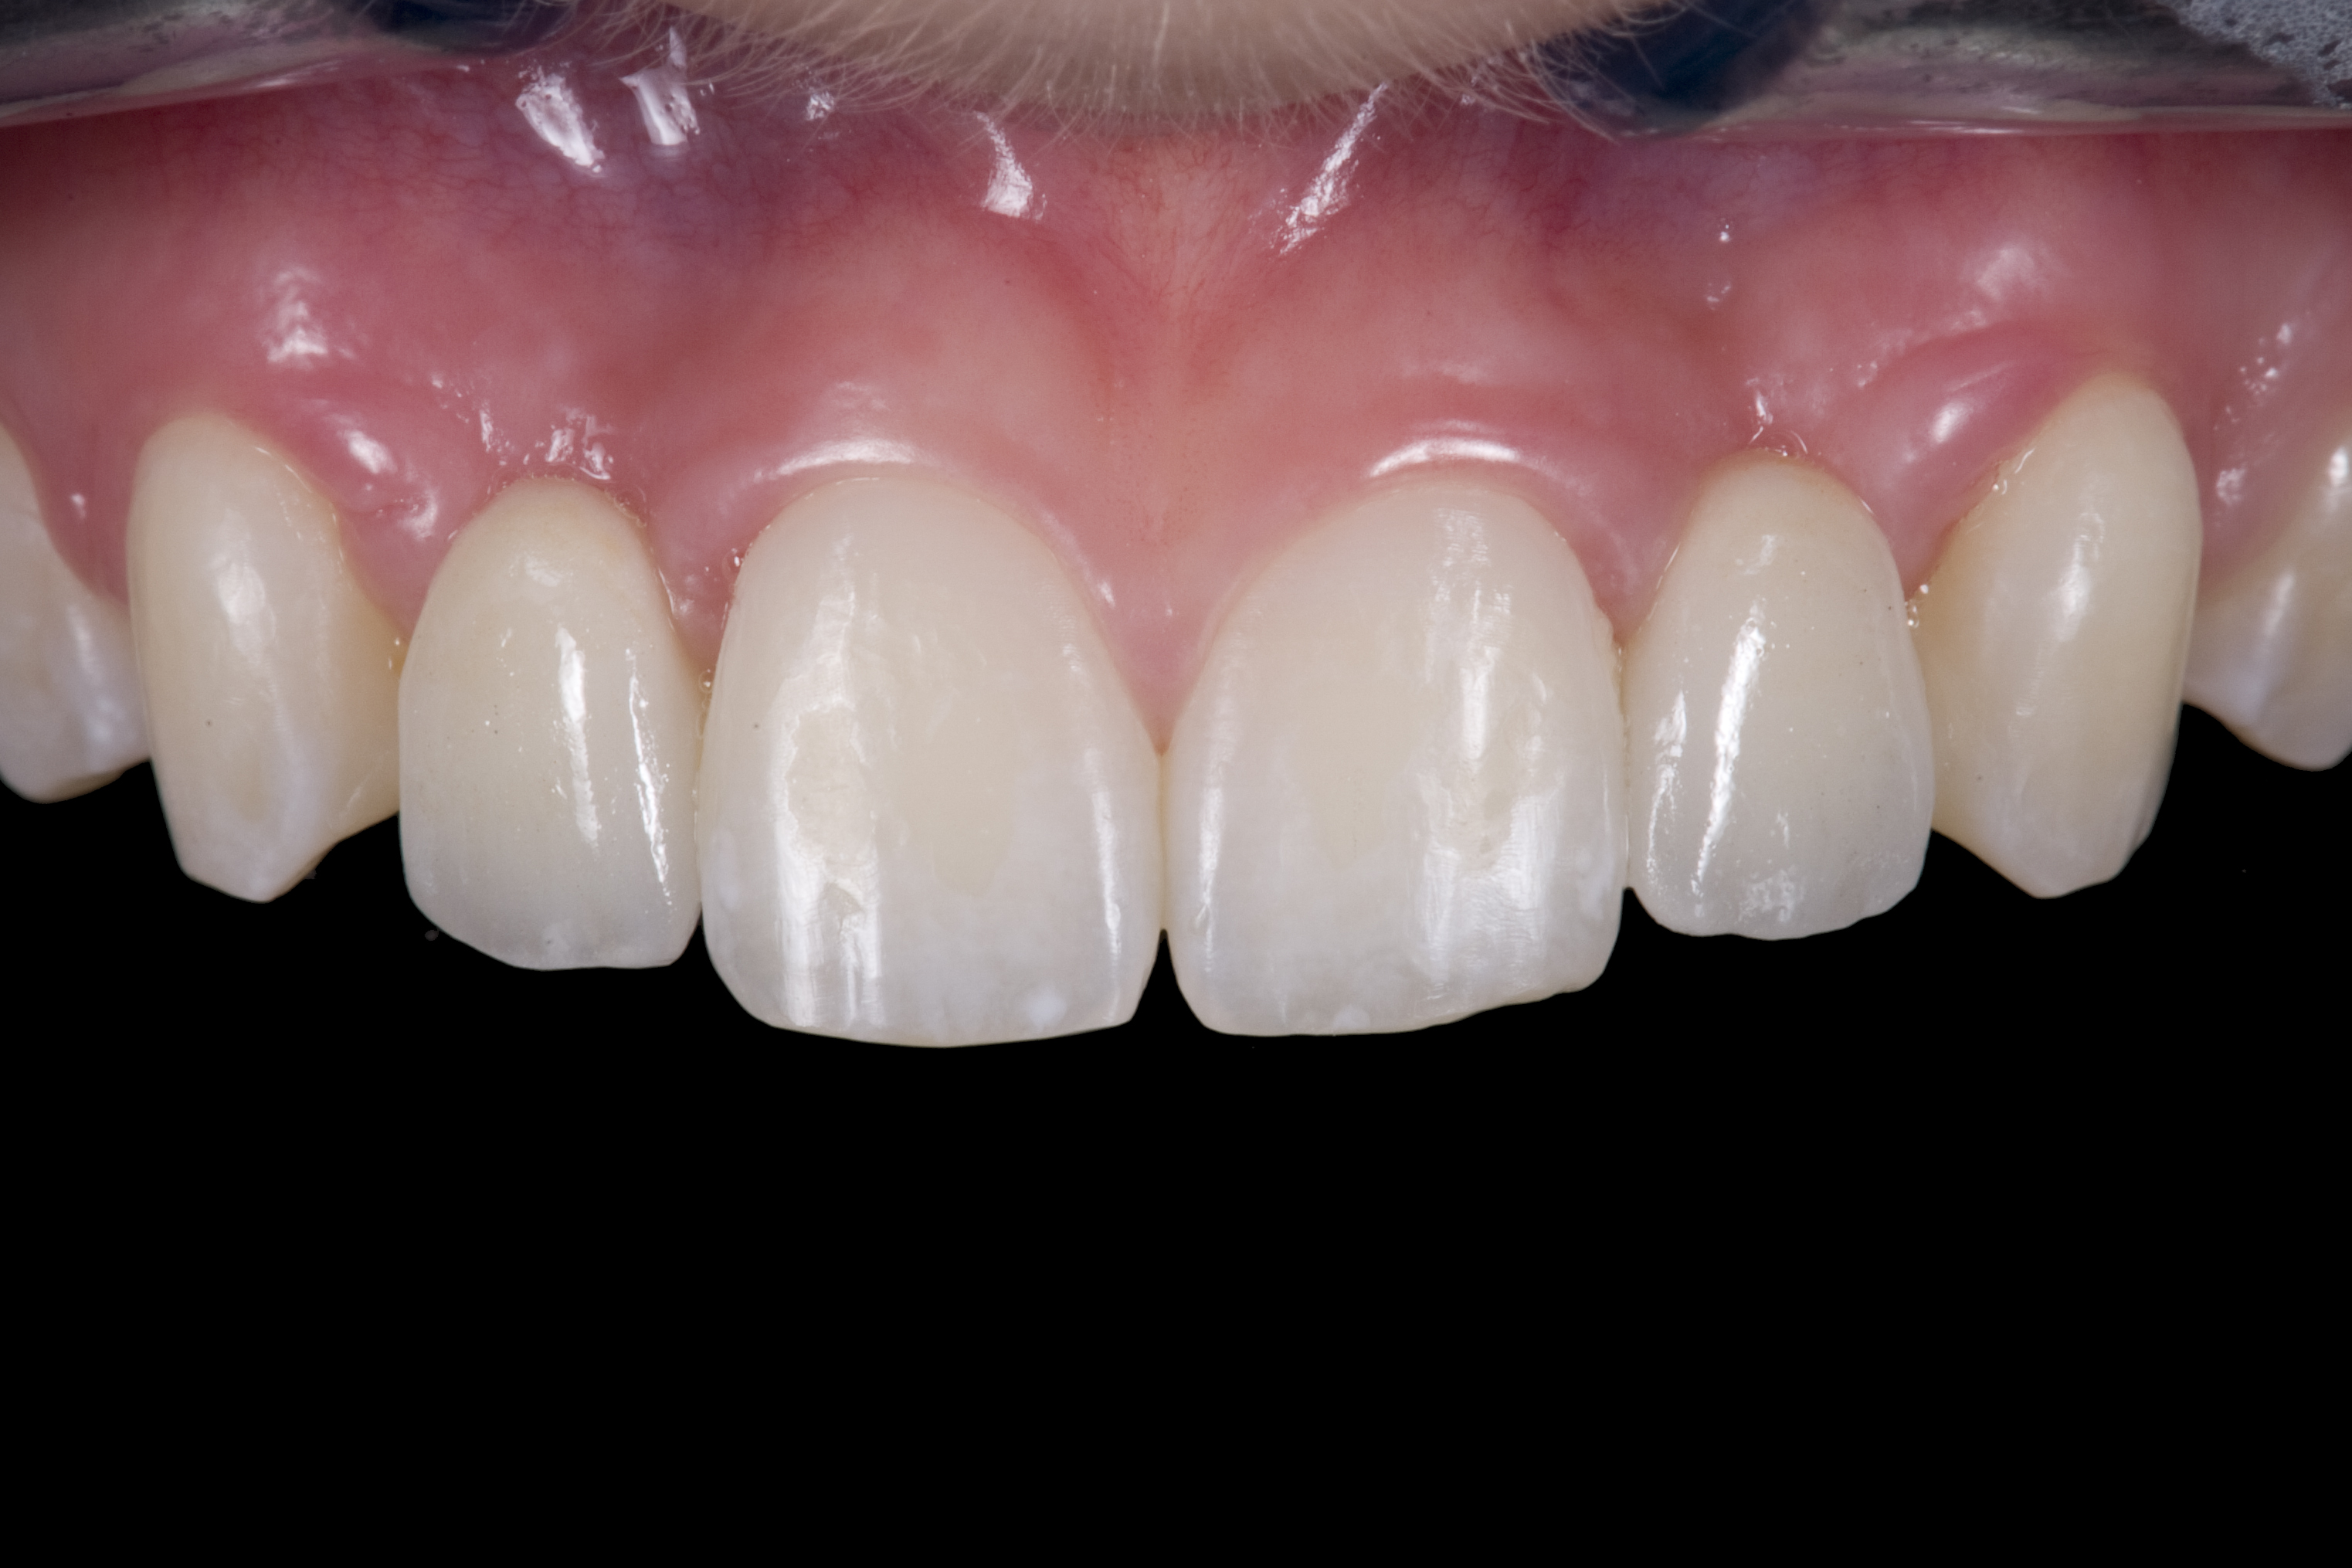

(21.) Smile view.

Figure 21

When the patient returned, the fit was evaluated in the mouth. Once verified, the internal surface of the framework was etched with a 9.5% hydrofluoric acid for 90 seconds and then salinized. After etching the enamel surface with phosphoric acid for 30 seconds and applying the primer (Single Bond Plus, 3M ESPE) to both the internal surface of the framework and the enamel, the zirconia bridge was bonded with a dual-cure resin cement (RelyX™ ARC, 3M ESPE). After the procedure, the patient ended up with a long-term, high-strength esthetic restoration advantaged by the bonding potential of fledspathic ceramic (Figure 20 through Figure 24). Six years after placement, the prosthesis had remained in place with no complications.